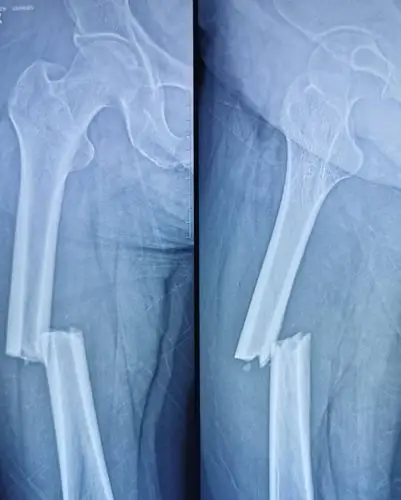

股骨干骨折ppt

股骨干骨折

股骨干合并股骨颈骨折一例